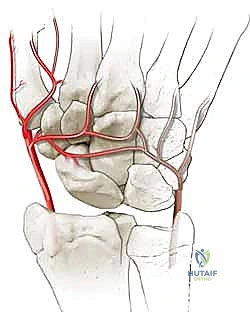

- الاستئصال الدقيق: باستخدام أدوات جراحية ميكروسكوبية دقيقة، يتم استئصال حوالي 3 إلى 4 مليمترات من القطب البعيد للعظم الزورقي. هذه الكمية كافية لمنع الاحتكاك مع عظم الكعبرة، وفي نفس الوقت تحافظ على استقرار الأربطة.

- تقييم المفصل: يتم فحص باقي عظام الرسغ للتأكد من عدم وجود خشونة متقدمة في أماكن أخرى.